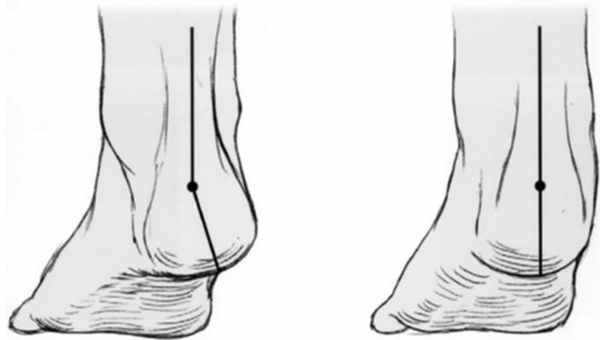

В первую очередь показано выполнение рентгенографии с нагрузкой в прямой и боковой проекции. При этом в прямой проекции выявляется неполное покрытие суставной поверхности головки таранной кости ладьевидной костью, увеличенный угол между таранной костью и первой плюсневой костью (угол Simmon), что встречается со 2 А стадии.

На боковых рентгенограммах определяется увеличенный таранно-плюсневый угол (угол Meary >4° свидетельствует о плоской стопе). Также снижается угол высоты пяточной кости (в норме 17-32°).